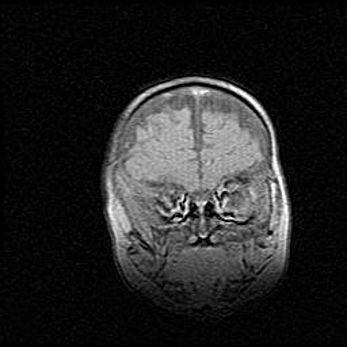

Множественные кисты обоих полушарий головного мозга, наибольшая из них в правой затылочной области. Ассиметричная атрофическая гидроцефалия.

Возраст: 7 месяцев

Вес: 5660 г

Пол: мужской

Окружность головы: 41,5 см

Срок гестации: 28-29 недель

Кисты головного мозга развиваются в результате многоочаговых некрозов вещества мозга и возникают вследствие перенесенной перинатальной инфекции, менингитов, энцефалитов, асфиксии, родовой травмы, расстройств мозгового кровообращения различного генеза. Образованию кист в веществе головного мозга плодов и новорожденных способствуют такие факторы, как высокое содержание в нем воды, недостаточная (или отсутствие) миелинизация и слабая астроглиальная реакция на повреждение.

Кисты могут сочетаться с гидроцефалией и другими поражениями головного мозга.